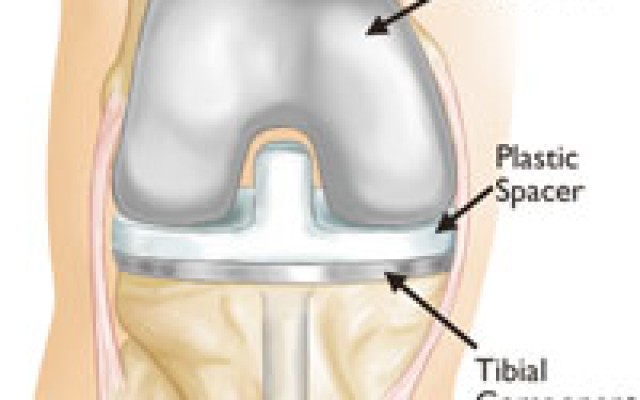

Posted in Dr Kaushik Hazratwala Blogs on Tuesday, 15 August 2017 by Kaushik Hazratwala

Total knee replacement has a very high success rate in relieving pain and bearing upon the ability to mobilize. Overall, 95% of these operations are highly successful and we know that at 10 – 15 years after the surgery 95% are still working very comfortably. In general, the knee replacement will last longer in older and lighter people. 1. Care your knee after knee replacement It will take...Is Hip replacement the best option for hip pain?

Posted in Dr Kaushik Hazratwala Blogs on Wednesday, 19 July 2017 by Kaushik Hazratwala

If you are considering a Total Knee Replacement or are having one soon, this video will help you understand what the surgeon will be doing. I should clarify that I no longer use rods inserted into the tibia and the femur as I use computer navigation. I do use bone cement to fix the implants to your bone. My patients usually stay in the hospital for 2 days and are walking the same day of the...Total Knee Replacement vs Resurfacing

Posted in Dr Kaushik Hazratwala Blogs on Wednesday, 19 July 2017 by Kaushik Hazratwala

With the invent of new surgical techniques and instruments Knee Replacements can now be performed almost like Resurfacing. Taking as little bone as possible and resurfacing it with the equal amount of metal and plastic. Total Knee Replacement vs resurfacing The attached picture is from a knee arthroplasty I performed today. This is the actual picture of the bone cuts I performed on the...Baker's Cyst of The Knee